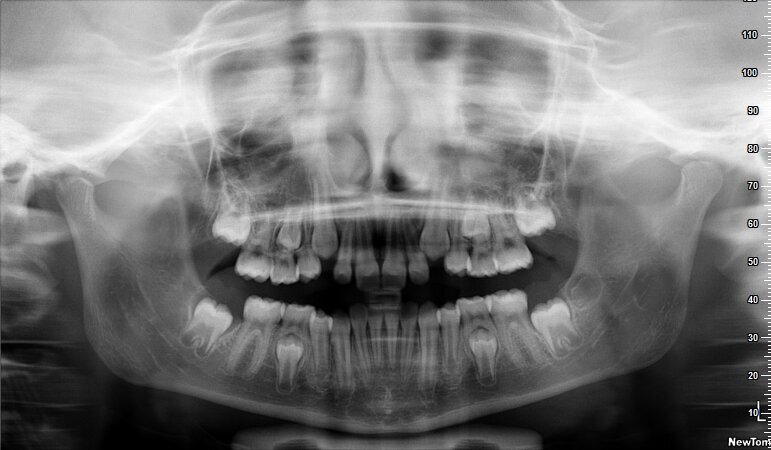

La piccola Sofia viene sottoposta a una prima visita ortodontica all’età di 8 anni, l’esame obiettivo (Figg. 1, 2) e l’ortopantomografia (Fig. 3) delle arcate dentarie evidenziano una mancanza di spazio per la corretta eruzione dei canini superiori (1.3-2.3).

Per motivi personali, i genitori di Sofia la sottopongono nuovamente alla nostra attenzione un anno dopo. Viene eseguita una nuova ortopantomografia (Fig. 4) che mostra un peggioramento del percorso eruttivo dei canini.

Fig. 3_Ortopantomografia iniziale.

Fig. 4_Ortopantomografia 1 anno dopo.